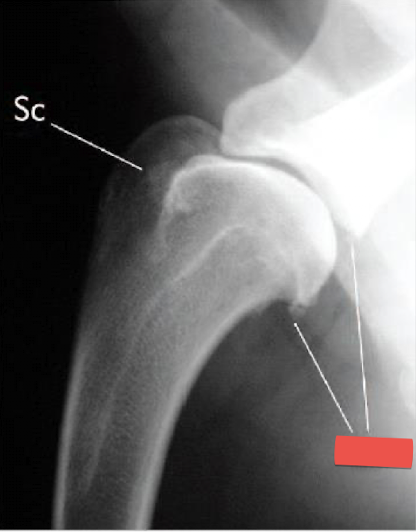

Wha condition is this image depicting? What is the red label showing?

Shoulder DJD

Osteophytes present on the caudal glenoid cavity and caudal humeral head